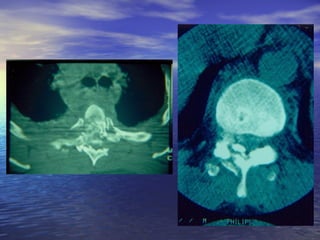

CC..TT..

ΣΣεε ππεερρίίππττωωσσηη::

AA..ΑΑννεεππααρρκκοούύςς εελλλλιιπποούύςς ααππλλοούύ

αακκττιιννοολλοογγιικκοούύ εελλέέγγχχοουυ

BB.. ΑΑδδυυννααμμίίαα εερρμμηηννεείίααςς ααππλλοούύ

ααππεειικκοοννιισσττιικκοούύ εελλέέγγχχοουυ

ΑΑππεειικκοοννιισσττιικκόόςς ΈΈλλεεγγχχοοςς CC..TT.. ΣΣεε ππεερρίίππττωωσσηη:: AA..ΑΑννεεππααρρκκοούύςς εελλλλιιπποούύςς ααππλλοούύ αακκττιιννοολλοογγιικκοούύ εελλέέγγχχοουυ BB.. ΑΑδδυυννααμμίίαα εερρμμηηννεείίααςς ααππλλοούύ ααππεειικκοοννιισσττιικκοούύ εελλέέγγχχοουυ